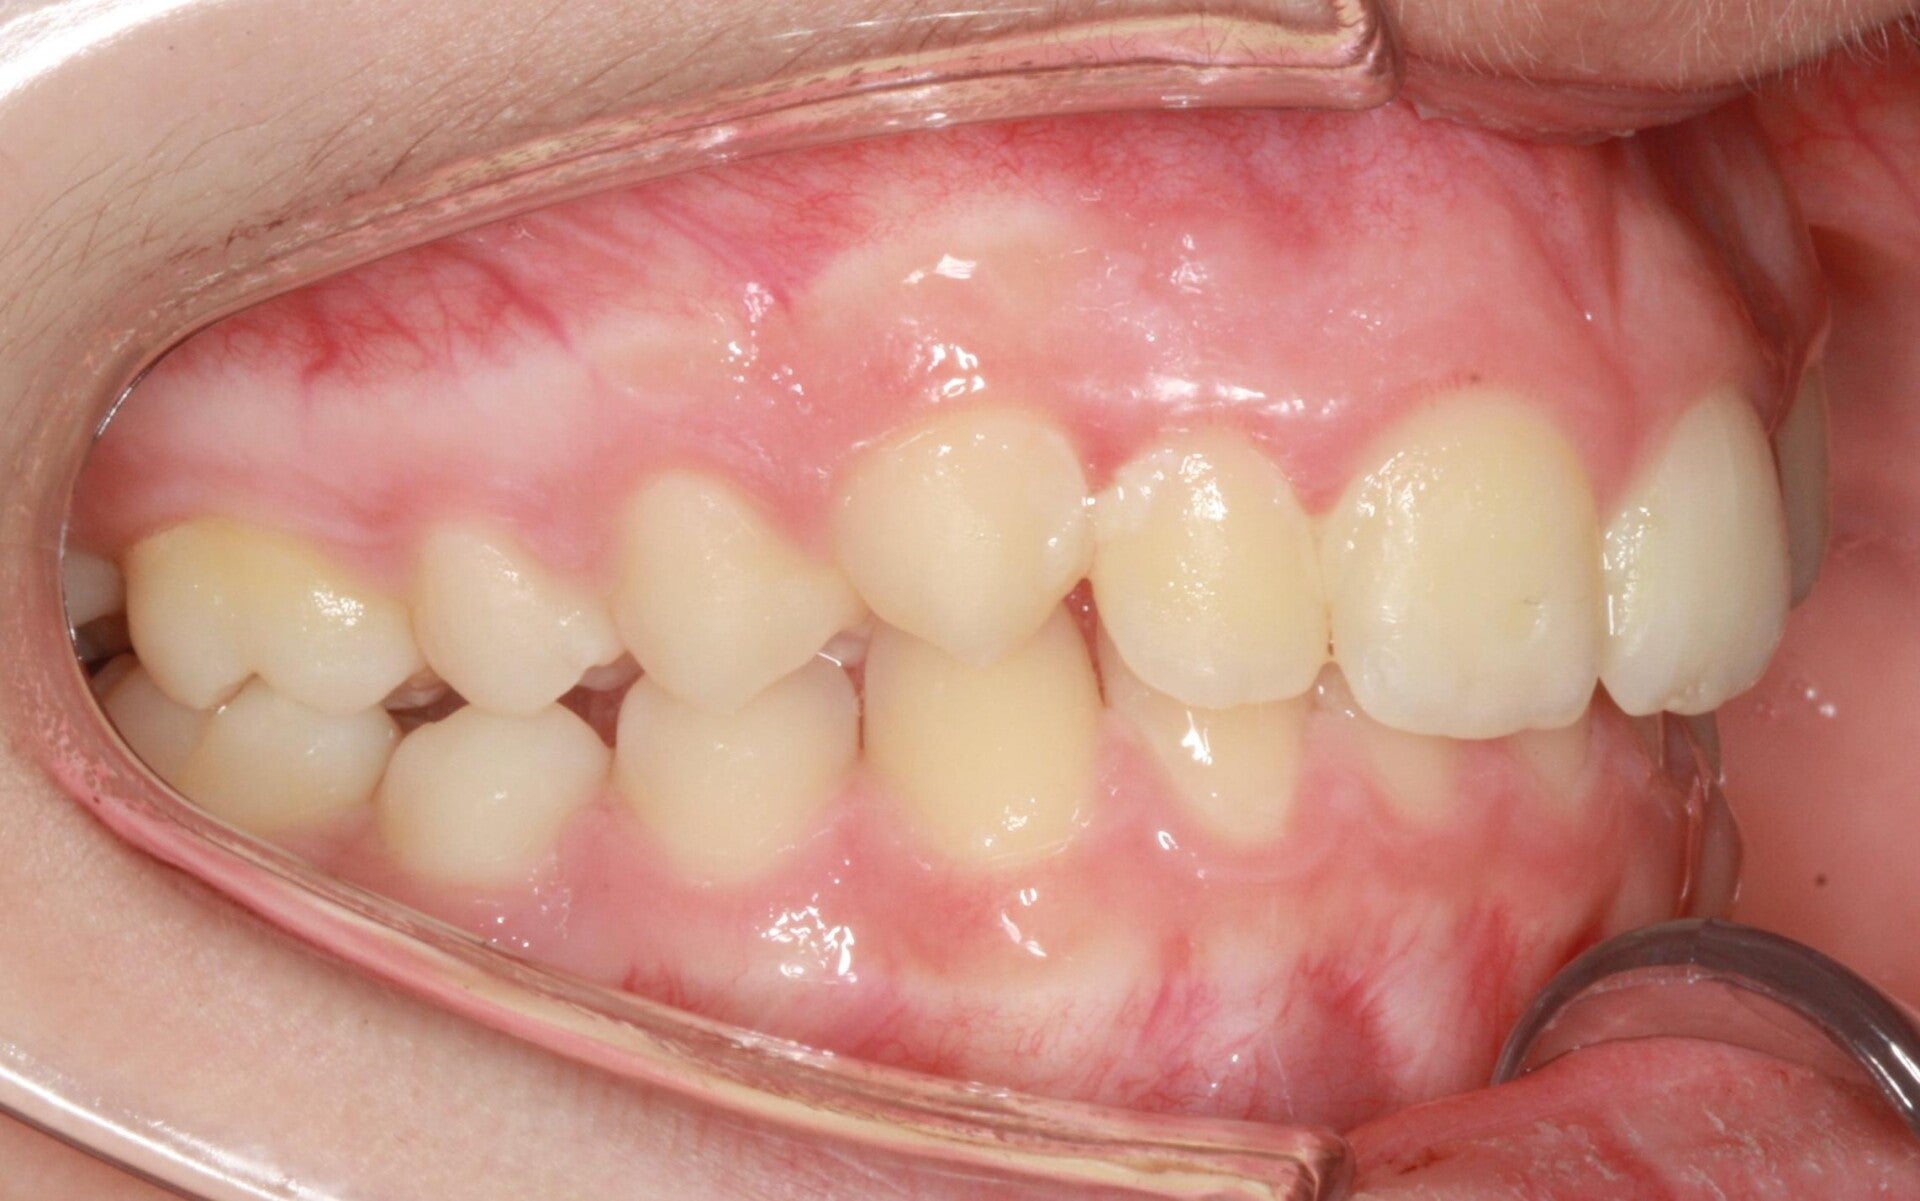

SECONDA CLASSE SUDDIVISIONE DESTRA

Questo mese vi presentiamo G.G. f. di15aa. Ha una seconda classe suddivisione destra molare e canina. richiesta Allineamento.

FOTO INIZIALI PRE TRATTAMENTO ORTODONTICO